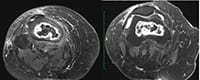

Paciente do sexo feminino, com 53 anos e quadro de dor crônica no joelho direito, principalmente na face anterior e medial. Ela refere piora da dor há uma semana, apresentando dificuldade na deambulação. Nega trauma e relata ter se submetido à cirurgia no tornozelo direito. Refere tratamento para asma brônquica com corticoide há anos.

Exames de imagem